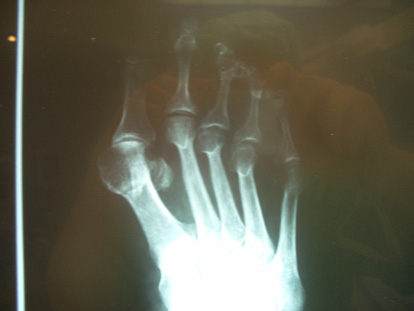

Radiografia pre-operatòria